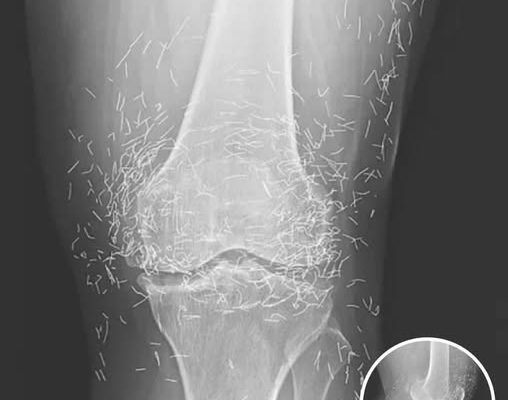

A routine X-ray revealed an unexpected surprise when doctors examined the knees of a 65-year-old woman suffering from severe joint pain. What they found was nothing short of astonishing — hundreds of tiny gold needles embedded deep in her tissue.

Acupuncture, a traditional therapy widely used in Asia, involves inserting thin needles into specific points on the body in an effort to relieve pain or treat illness. In this case, however, doctors say the gold needles were left behind intentionally as part of her treatment plan, designed to deliver continuous stimulation to the affected area.

There are other complications as well. Needles lodged in tissue can interfere with medical imaging. “They can obscure parts of the anatomy on an X-ray,” Guermazi noted. Even more alarming, patients with metal fragments in their bodies should never undergo an MRI, as the magnetic force could cause the needles to move — potentially puncturing blood vessels and causing life-threatening damage.

As for the South Korean woman, her case was recently documented in the New England Journal of Medicine. While the needles may have been intended to help, her X-rays tell a cautionary tale about the potential risks of extreme alternative therapies.